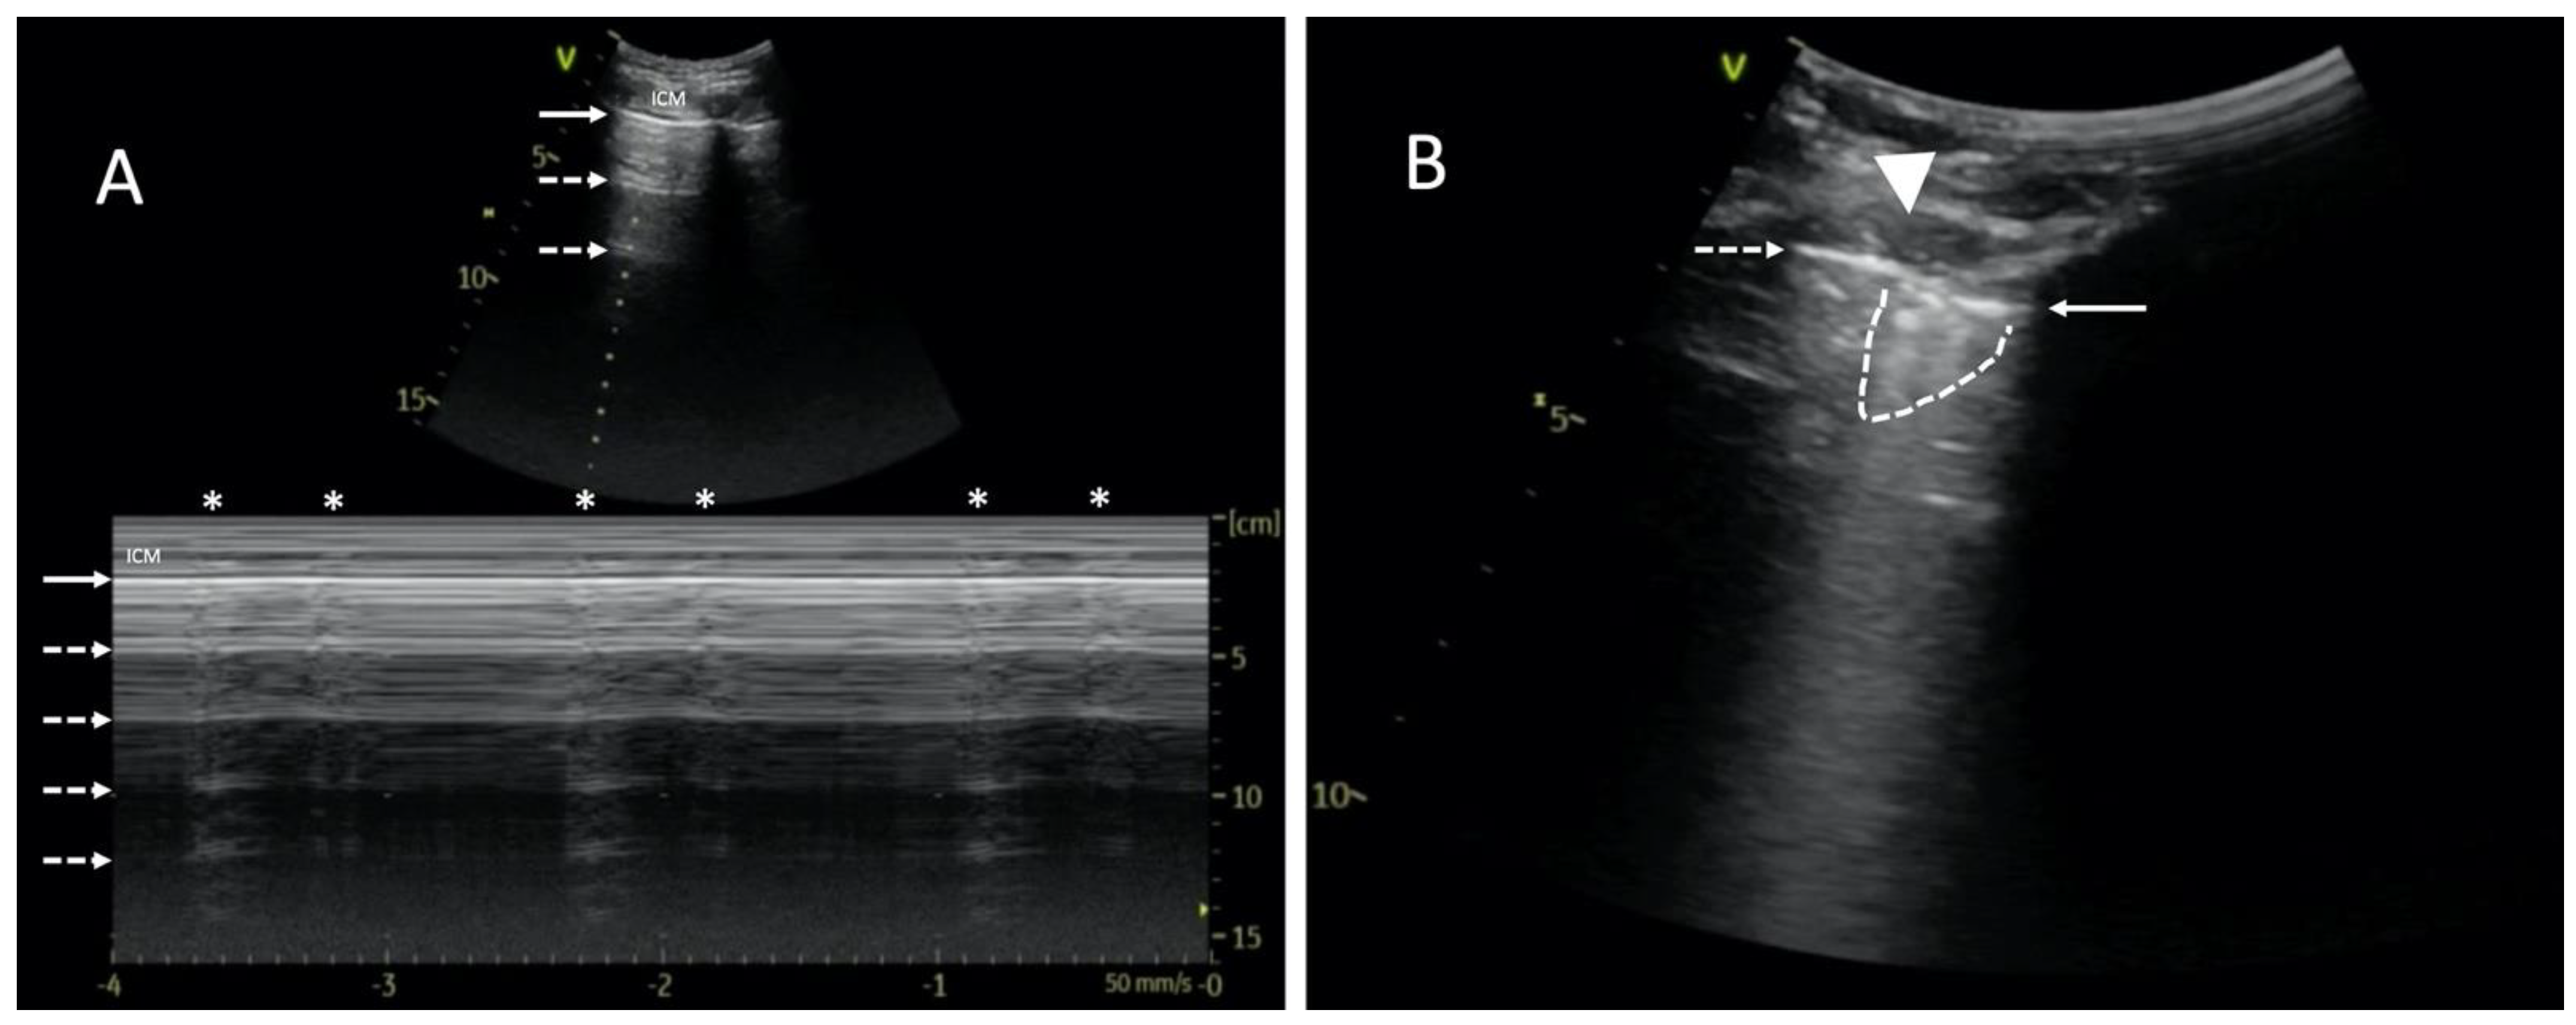

The mechanical ventilation of ARDS patients is likely to make it challenging due to high PEEP and small tidal volumes. Therefore, the absence of pleural sliding cannot be the only symptom determining the diagnosis of pneumothorax. In cases of diminished lung sliding, a high-frequency linear transducer should be used to better visualize the pleura. Alternatively, M-mode combined with real-time ECG may be useful to search for the so-called lung pulse. A “pseudo” lung pulse may result from intercostal muscle contraction in a spontaneously breathing patient, but unlike a real lung pulse, it starts above the pleural line, passes down crossing it, and does not correlate with the heart rate (Figure 1A; Video S1A) [3].

Figure 1.

Point-of-care lung ultrasound of a 59-year-old male with severe ARDS, mechanically ventilated (Bilevel; FiO2 60%; PL10 cmH2O; PH15 cmH2O). A left-sided pneumothorax occurred after pacemaker implantation. The study was performed using a 1.8–6 MHz convex probe. (A) Muscle contractions imitate lung pulse and hinder the diagnosis of pneumothorax. LUS examination revealed horizontal reverberation artifacts (dashed arrows). M-mode image shows a barcode sign with visible vertical artifacts (asterisks). Unlike a real lung pulse, the artifacts originate from the intercostal muscles (ICMs). Therefore, they start superficially to the pleural line and move down, passing the pleural line (solid arrow). Please see Video S1. (B) Lung point is a pathognomonic sign of pneumothorax and can be fully seen in Video S1B. This static image shows both pleural laminae separated from each other. As a result of pneumothorax, only the parietal pleura is visible on the left side (indicated with a dashed arrow). On the right side, a part of the lung with fragmented pleural line (solid arrow) and subpleural consolidation (dashed line) can be seen. The contact area is called the lung point (triangle).

The following are available online at https://www.mdpi.com/article/10.3390/diagnostics14020206/s1, Video S1A. A 59-year-old male with ARDS, mechanically ventilated (Bilevel; FiO2 60%; PL10 cmH2O; PH15 cmH2O). Point-of-care LUS using a 1.8–6 MHz convex probe in B-mode shows extensive intercostal muscle (ICM) contraction, questionable pleural sliding (arrow), and horizontal reverberation artifacts formed on the air/tissue boundary (dashed arrow). In M-mode, a barcode sign with vertical artifacts is observed (asterisk). Unlike a real lung pulse, the artifacts originate from the intercostal muscles, above the pleural line. Video S1B. Point-of-care LUS using a 1.8–6 MHz convex probe. On the left side of the LUS image, pneumothorax is visible with abolished lung sliding (dashed arrow) and no vertical reverberation artifacts. A part of the lung with fragmented pleural line (arrow) and subpleural consolidation (dashed line) appears suddenly and transiently on the right side of the ultrasound image. The contact area is called the lung point (triangle). Video S2. A 59-year-old smoker with COPD and severe ARDS. All pictures were obtained with a 1.8–6 MHz convex probe during vv-ECMO therapy and baby lung ventilation (Bilevel; FiO2 40%; PL10 cmH2O; PH 5 cmH2O; Vt~100–150 mL). On the left side of the LUS image, pneumothorax can be observed, with an irregular line of the parietal pleura (dashed arrow), abolished pleural sliding, and no horizontal reverberations developed at the air/tissue boundary. A cyclically appearing fluid (asterisk) and a lung with a visible irregular pleural line (arrow) and consolidation (dashed line) can be seen on the right side. The contact point of both is called the hydro-point (triangle). Video S3. A 24-year-old male with human immunodeficiency virus (HIV) infection and ARDS due to suspected atypical bacterial pneumonia. Ventilated with guaranteed tidal volume (Bilevel Volume Guarantee; FiO2 100%; Vt 400 mL; PEEP 6 cmH2O; PIP 30 cmH2O). Point-of-care LUS with a 1.8–6 MHz convex probe. Image of blurred and fragmented pleural line (arrow) with visible subpleural consolidations (dashed lines). In addition, coexisting horizontal pleural reverberations (dashed arrow) with abolished pleural sliding and comet tail artifacts (asterisks) most likely emerging from subpleural structures. The image corresponds to the bullous emphysema in the CT scan, as shown in Figure 3B.